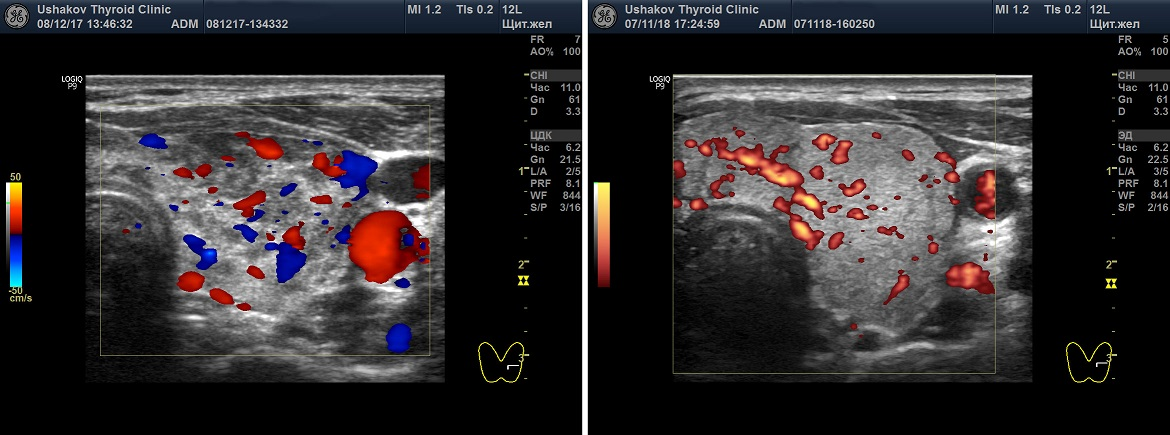

Слева -ЦДК (красные и синие элементы показывают сосуды и направление тока крови). Справа - ЭДК.